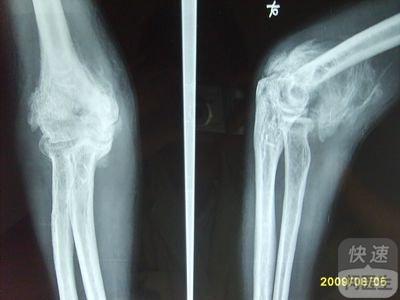

核心提示:骨化性肌炎疾病是一种危害身体健康的疾病,而且此疾病还会并发肌肉破裂,严重者还会导致残废,所以患者一定要引起重视,当发现自己患有此疾病时,一定要及时的去医院治疗,然后配合医生的治疗措施,争取早日的康复。  骨...